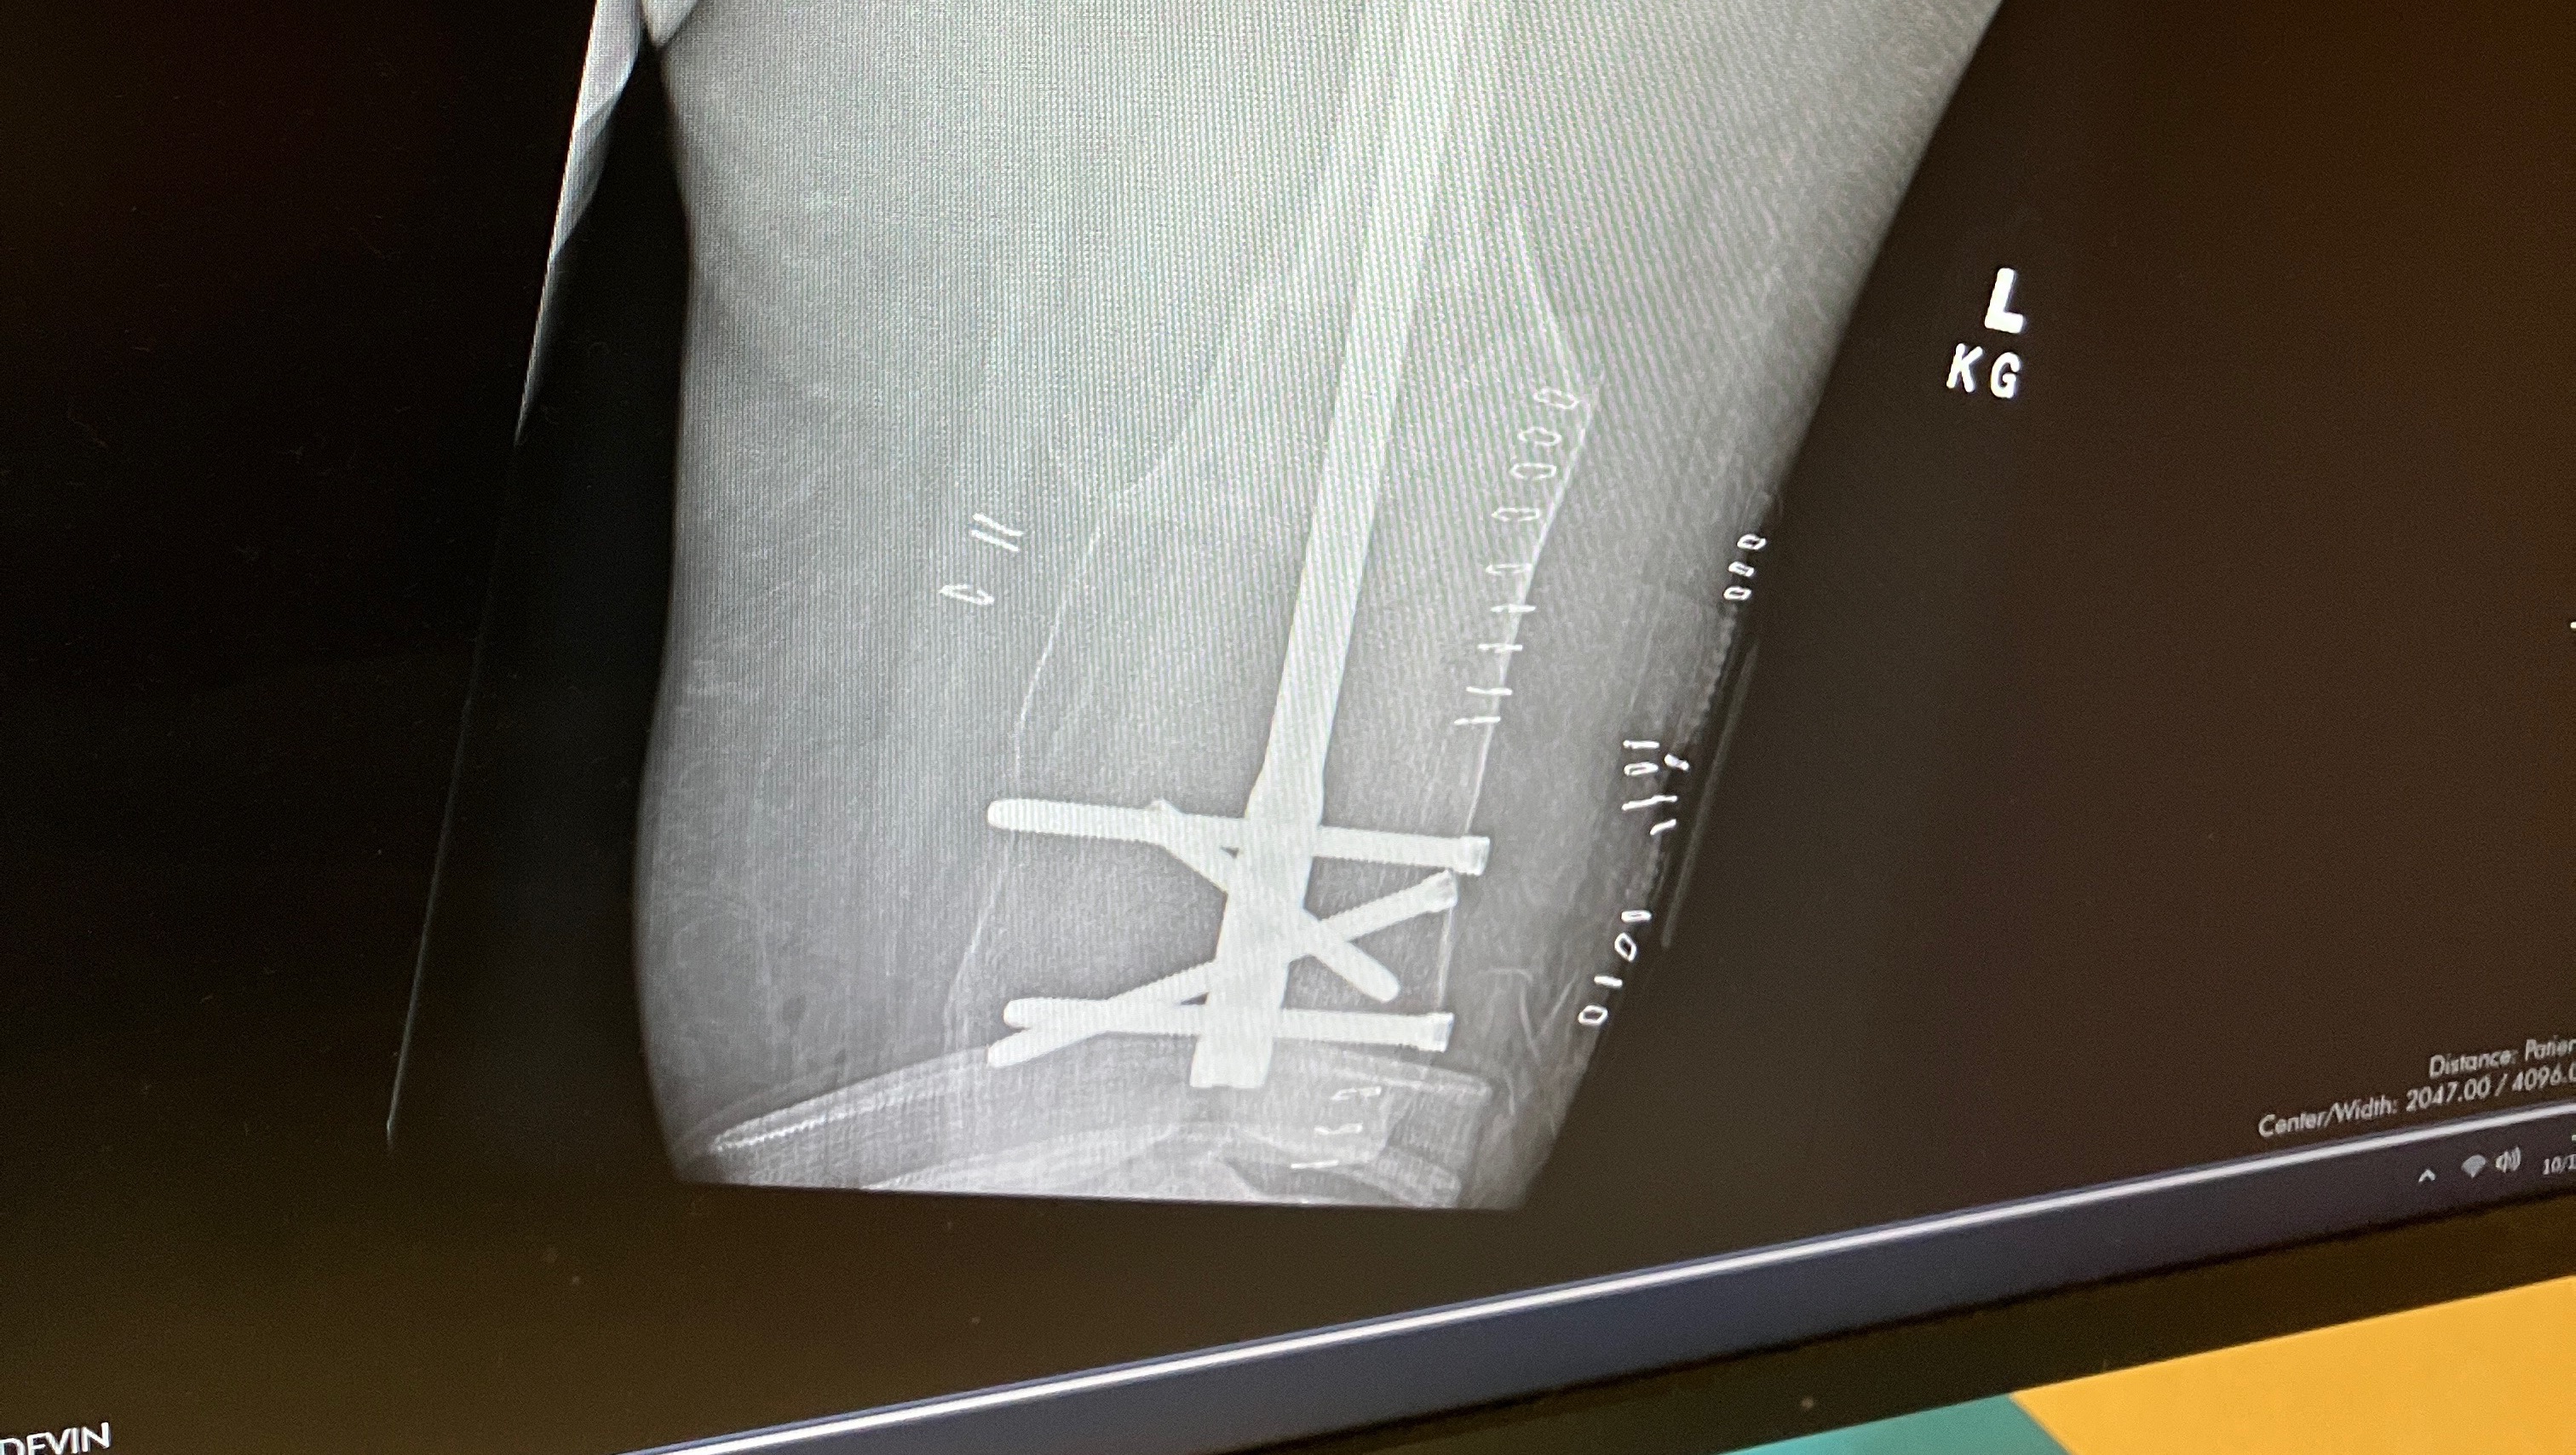

Update- Tony is still fighting his fight! Tony is currently doing oral chemotherapy which is easier on him. He has been able to stay out of the hospital since starting the oral chemotherapy which is amazing news however Lisa is now hospitalized. Two months ago when Lisa was at work she fell and injured her knee. She has been since been off She was finally scheduled for surgery on October 15th! After leaving her pre-op appointment she fell in the waiting room and broke her leg in three different places. She had emergency surgery on her leg that same night. She was just transferred to a rehab facility while she heals. Doctors say she will be out of work for 8 months to a year!